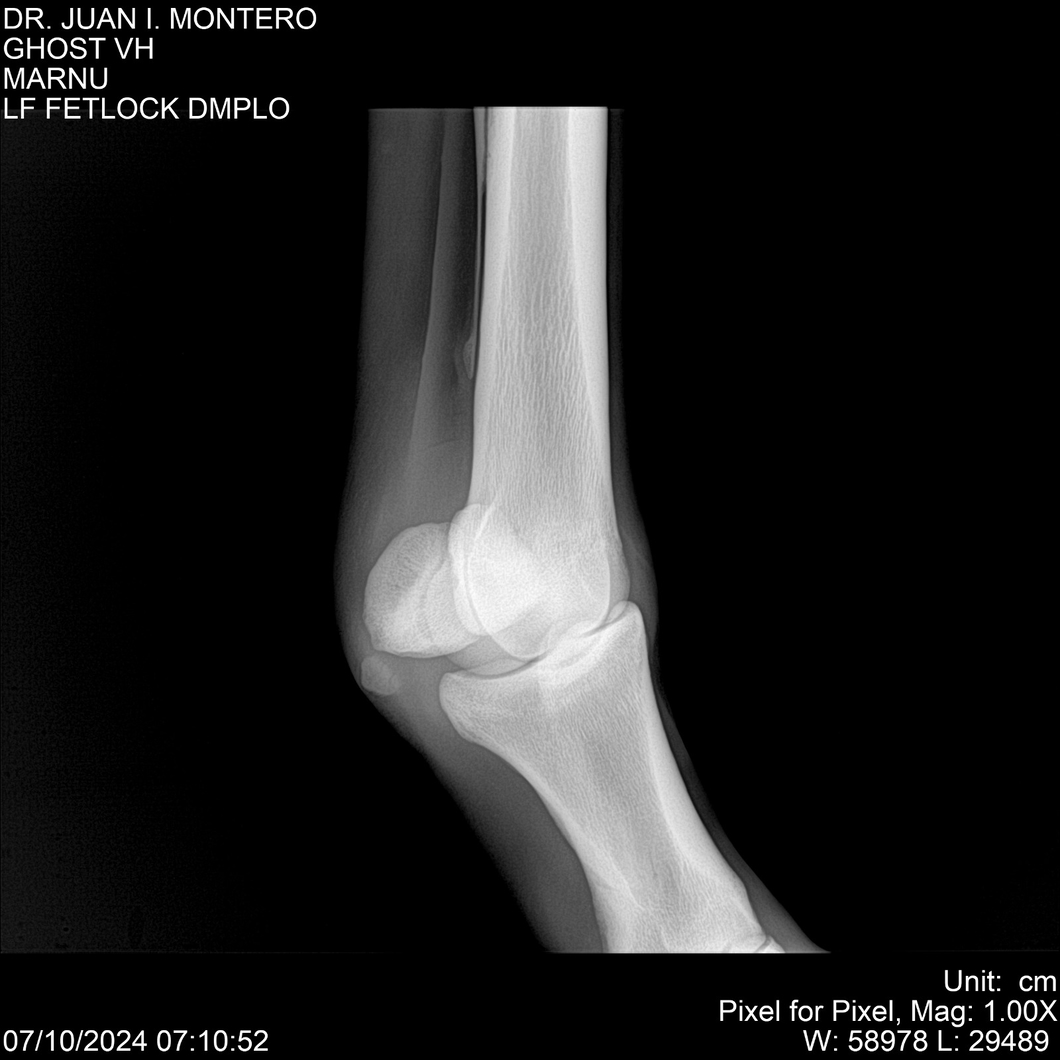

LOTE 15, GHOST VH 🔥 🔥 🔥 Lote Anterior Volver al remate Lote Siguiente Ficha Contacto Montevideo - Ficha del Lote Identificador: #282525 Categoría: Yeguarizos Montevideo - 69 Visualizaciones ClicData Contacto Empresa: Abelenda N. R., Walter Hugo Nombre*: Teléfono* : E-mail* : Mensaje Enviar Registrese gratis Este contenido Exclusivo está disponible sólo para usuarios registrados Ingresar